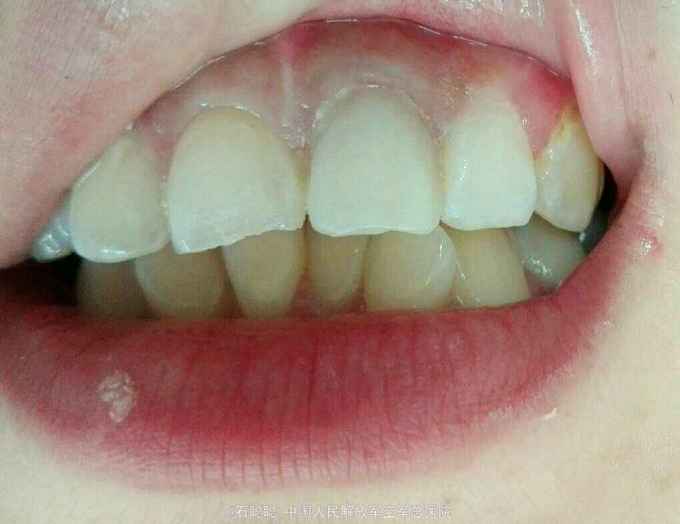

诊断:21牙体缺损 12慢性根尖周炎 治疗计划:21全冠修复 12根管治疗后全冠修复 处置:21备牙,取模,比色A3,制作临时冠,调合,粘接 一周后复诊: 检查:21临时冠完整在位,无松动,叩痛-,牙龈未见异常 处置:21去除临时冠,试戴银钯合金烤瓷冠,调合、磨光,粘接

讨论:根管治疗后的牙齿由于血红素分解产物进入牙本质小管导致牙体变色,尝尝成为患者就诊的主诉,这个患者由于两个上颌中切牙存在切缘不均匀磨耗,形态不对称,颜色纠正效果较好,龈缘密合,患者很满意。嘱患者择期治疗12其36、46。